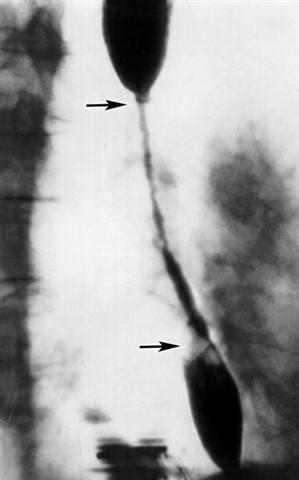

Рис. д). Рентгенологическая картина при различных заболеваниях и поражениях пищевода, сопровождающихся дисфагией: протяженное рубцовое сужение пищевода (указано стрелками), вызванное его ожогом.